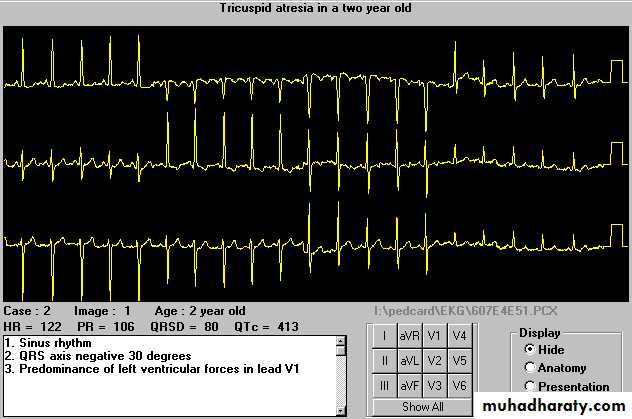

Tricuspid Atresia- EKG

Very characterestic : Left axis deviation